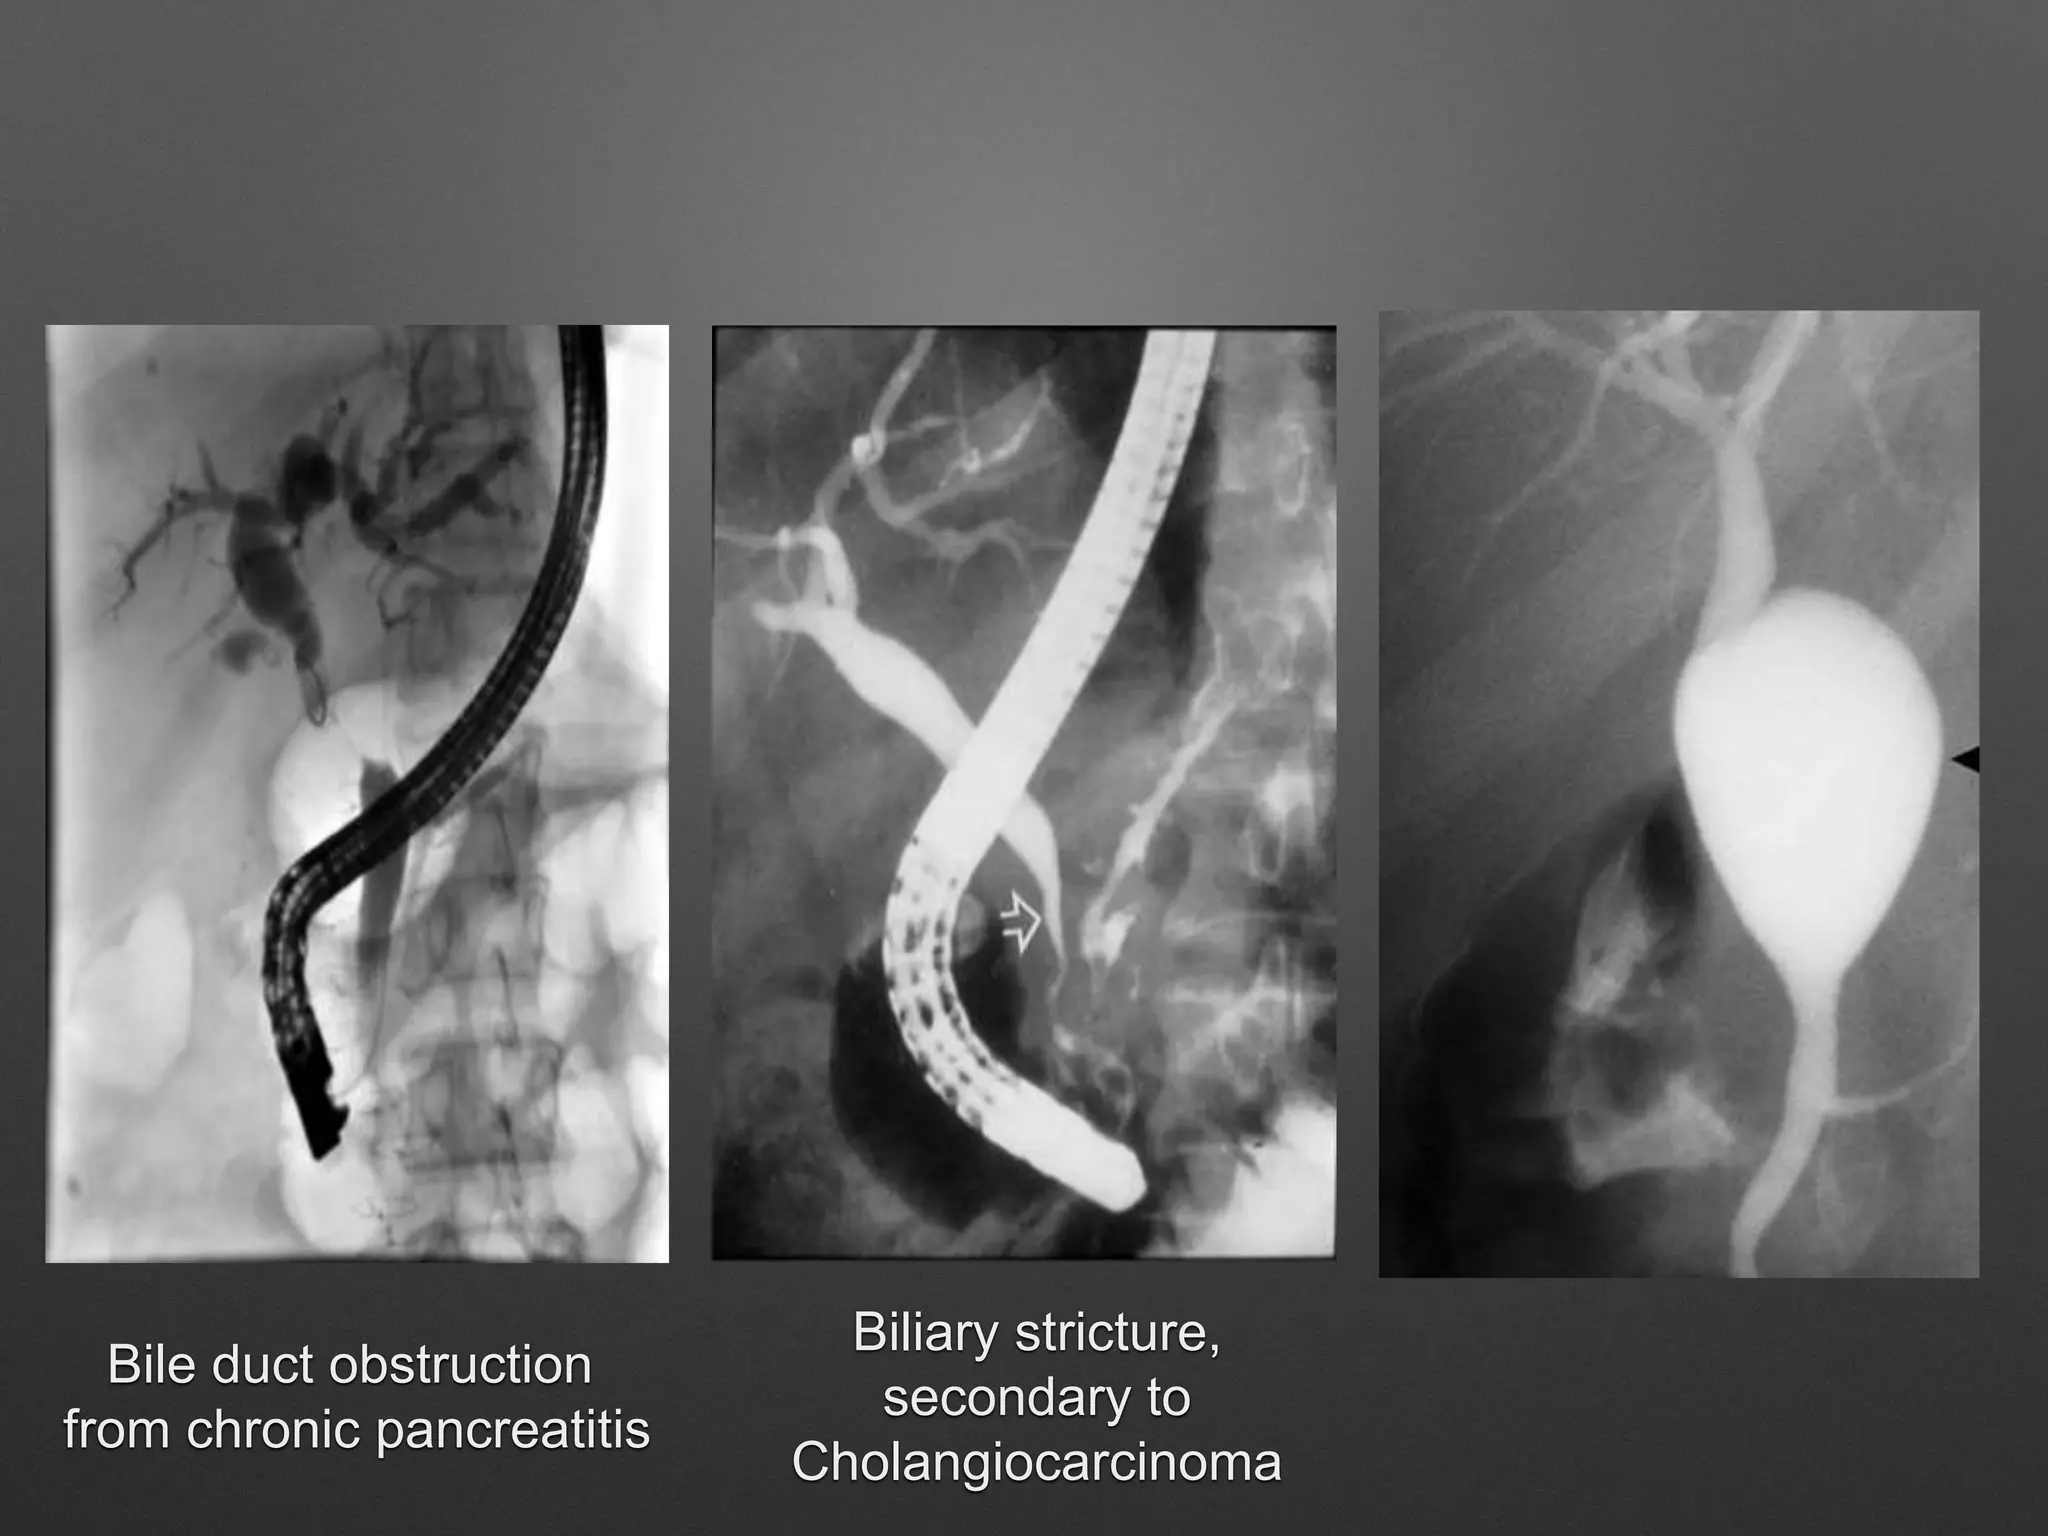

Bile duct obstruction

from chronic pancreatitis

Biliary stricture,

secondary to

Cholangiocarcinoma

Bile duct obstruction fromchronic pancreatitis Biliary stricture, secondary to Cholangiocarcinoma